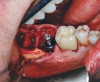

Fig 14. Extraction site, with mesiobuccal bone dehiscence concealed under soft tissue, and immediate implant placement with ISQ post in position.

Figure 14

After clinical evaluation, CBCT assessment with a dynamic navigation fiducial was followed by planning for immediate implant placement. This included evaluation of inferior alveolar nerve position, undercut, buccal plate dehiscence, implant positioning in the defect, and retention screw path. The patient was taken to surgery under intravenous and local anesthesia with removal of the mandibular right second and third molar teeth. The sites were aggressively debrided with a mesiobuccal root dehiscence noted, and site development followed with the use of dynamic navigation (Figure 13).

Implant insertion (5.5 mm x 13 mm NobelActive®, Nobel Biocare, nobelbiocare.com) gave excellent primary stability, was level with the residual buccal bone, and achieved an ISQ reading of 74 (Figure 14). Lingual bone contouring (to avoid abutment impingement) was followed with implant gap grafting, which included the mesiobuccal root defect and adjacent extraction site, using mineralized particulate cortico-cancellous allograft (enCore®, Osteogenics Biomedical). A 7 mm x 8 mm poly-ether-ether-ketone (PEEK) healing abutment was inserted and the access opening filled with PTFE tape (Figure 15). A single layer of dHACM (Figure 16) was inserted on the bone graft with tissue forceps and saturated with saline to seal the implant-soft-tissue interface. Suturing with 4-0 chromic gut secured the site, using inverse "figure 8" at the anterior and interrupted sutures at the posterior margin (Figure 17).